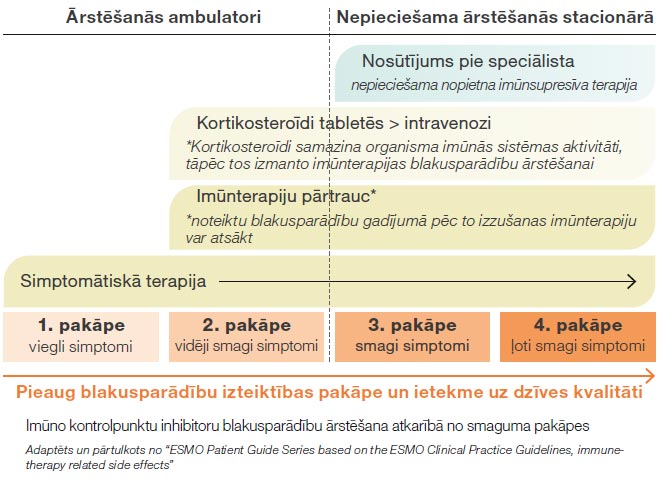

Pretēji citotoksiskai ķīmijterapijai imūnterapija stimulē, nevis nomāc organisma imunitāti, tāpēc arī imūnterapijas blakusparādības ir saistītas nevis ar imunitātes novājināšanu, bet ar tās stimulāciju. Imunitātes stimulācija var notikt ne tikai pret vēža šūnām, bet arī pret organisma normālām šūnām. Tas izpaužas kā iekaisums, ko organisms izraisa pats pret sevi: ādas iekaisums (dermatīts), locītavu iekaisums (artrīts), vairogdziedzera iekaisums (tireoidīts), zarnu iekaisums (kolīts), plaušu iekaisums (pneimonīts) u.c. (skat. tabulu) Imūnterapijas blakusparādības, ja parādās, tad visbiežāk pirmo trīs mēnešu laikā no terapijas sākuma. Blakusparādības iedala smaguma pakāpēs, un visbiežāk novēro viegli- vidēji izteiktas blakusparādības. Tās ir labi ārstējamas ar kortikosteoīdiem – pretiekaisuma medikamentiem tablešu vai injekciju veidā.

Pretēji citotoksiskai ķīmijterapijai imūnterapija stimulē, nevis nomāc organisma imunitāti, tāpēc arī imūnterapijas blakusparādības ir saistītas nevis ar imunitātes novājināšanu, bet ar tās stimulāciju. Imunitātes stimulācija var notikt ne tikai pret vēža šūnām, bet arī pret organisma normālām šūnām. Tas izpaužas kā iekaisums, ko organisms izraisa pats pret sevi: ādas iekaisums (dermatīts), locītavu iekaisums (artrīts), vairogdziedzera iekaisums (tireoidīts), zarnu iekaisums (kolīts), plaušu iekaisums (pneimonīts) u.c. (skat. tabulu) Imūnterapijas blakusparādības, ja parādās, tad visbiežāk pirmo trīs mēnešu laikā no terapijas sākuma. Blakusparādības iedala smaguma pakāpēs, un visbiežāk novēro viegli- vidēji izteiktas blakusparādības. Tās ir labi ārstējamas ar kortikosteoīdiem – pretiekaisuma medikamentiem tablešu vai injekciju veidā.